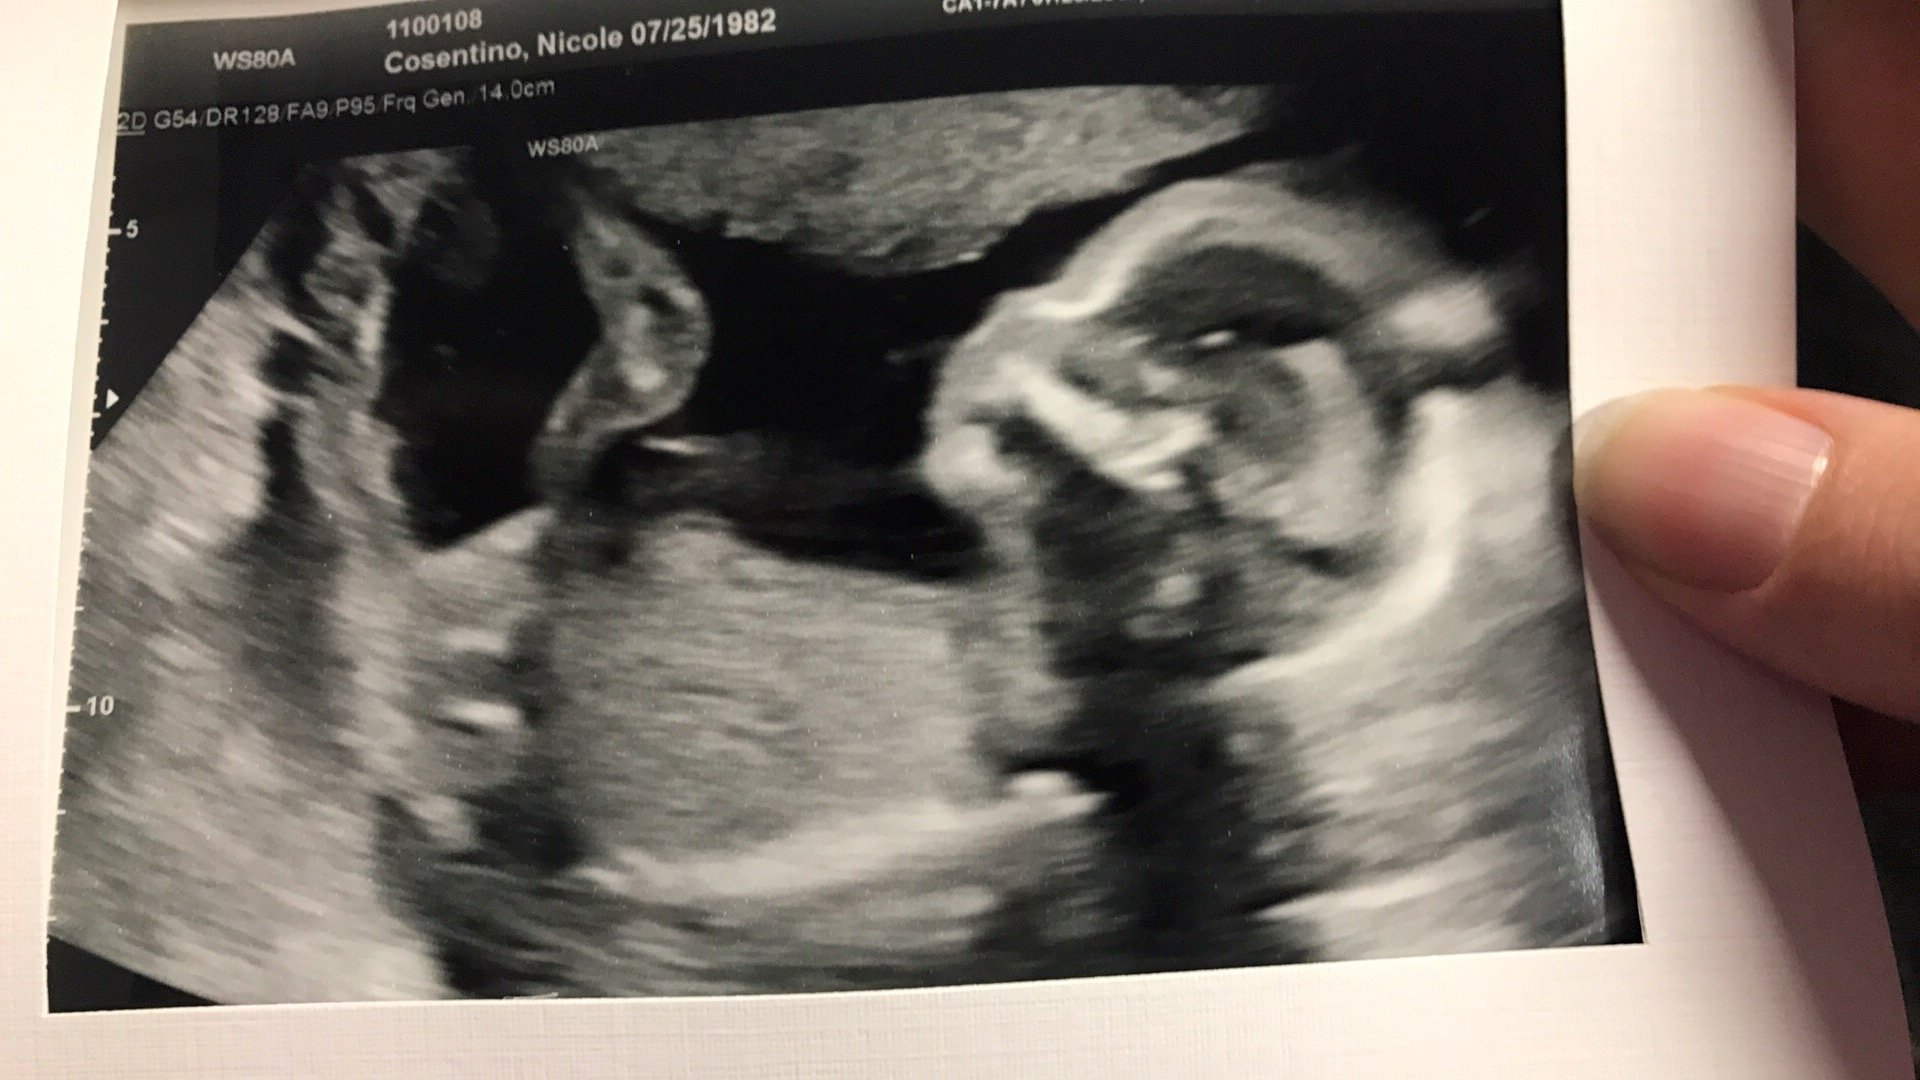

Well, it's official. It's a GIRL. I turned to DH when the tech told us and said "I was right!". LOL.

She (I can't believe I get to say that now) is measuring between my due date based on my LMP and my due date based on my ovulation date (I definitely kept track). So, we're looking at a kid that will most likely be late. Awesome. Everything looked fine, but the doctor wants me to go back in 3 weeks for a follow-up ultrasound. Some of the pictures weren't as clear as the doctor wanted. Fine with me. I get to see the little one again.

She also appears to have big feet. LOL.